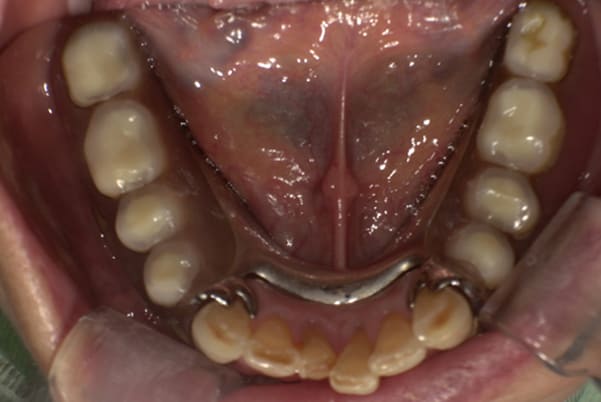

下顎治療前

治療前の入れ歯の奥歯は、治療後の義歯と比較しても分かるように、歯が削れ平らになった状態です。

これにより奥歯のかみ合わせは低くなり、前歯のみが強くあたり、かみ合わせにより上の前歯大きな負担がかかっていたことにより、上の前歯が折れたことが考えられます。